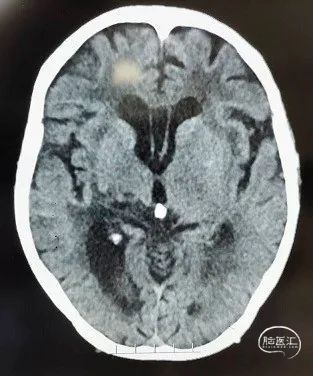

03 术前影像资料

左侧大脑中动脉供血区未见明显低密度病灶,且外侧裂可见大脑中动脉点征,支持大脑中动脉闭塞。

DWI成像显示左侧基底节区可见多发片状高信号影,FLAIR像未见新鲜病灶显影,皮层均未见受累,考虑为侧枝循环较为丰富,但与患者临床症状不相符,既影像与临床不匹配、DWI/FLAIR不匹配。

MRA显示左侧大脑中动脉M1段起始处闭塞。

术后24小时复查头颅CT未见明显出血及低密度病灶,患者NIHSS评分为4分。